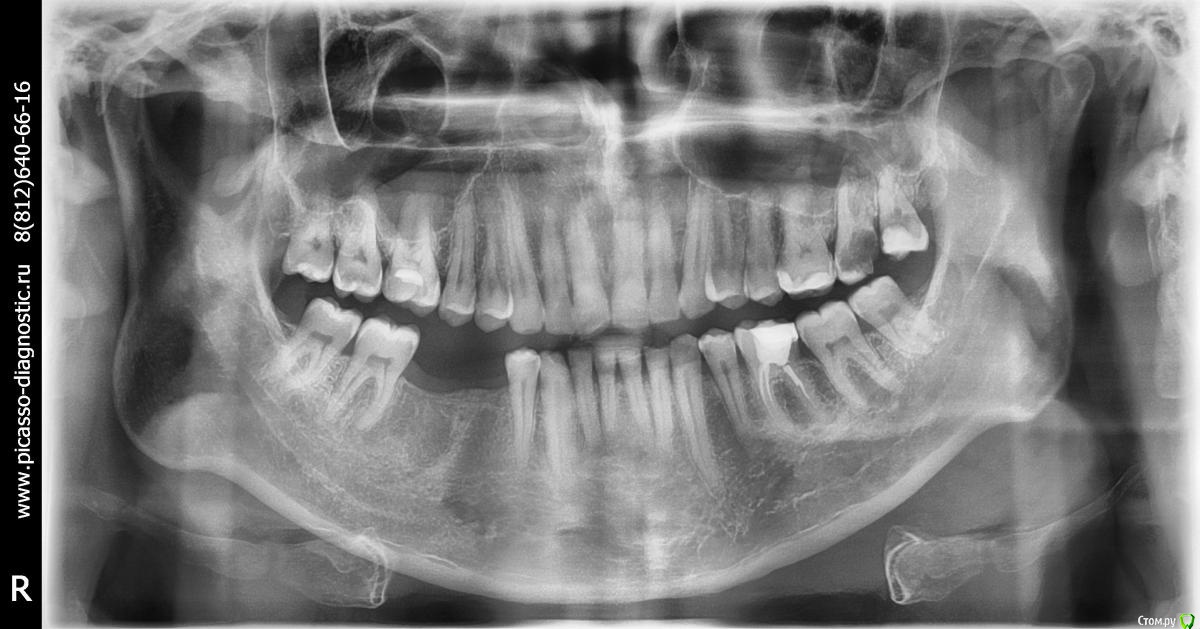

LOST Опубликовано 14 октября, 2015 Поделиться Опубликовано 14 октября, 2015 Добрый день.Подскажите пожалуйста. Врач рекомендует поствить мост на нижней челюсти, где отсутствуют два зуба. См. фото.Сказал что придется депульпировать два соседних опорных зуба - такая техника установки моста. С этими зубами у меня проблем нет, кроме кариеса, который планировал лечить.Не знаю что делать. Стоит ли ставить мост? Ведь в этом случае два опорных зуба станут "мертвыми" ( без нервов ).Чем грозит отсутствие зубов на моей нижней челюсти, если я все же не поставлю мост? Их там нет уже 4 года и их отсутствие особых неудобств не доставляет.Дайте пожалуйста совет ставить или нет? Спасибо. Ссылка на комментарий

IvanK Опубликовано 15 октября, 2015 Поделиться Опубликовано 15 октября, 2015 + обратите внимание на другие зубы Ссылка на комментарий